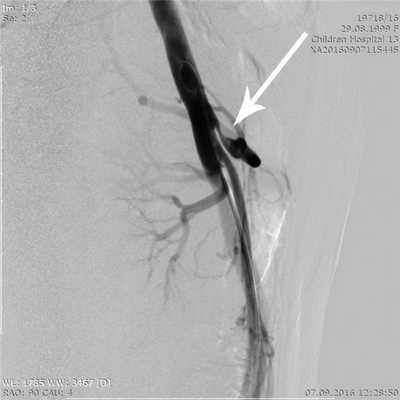

Ангиография является наиболее инвазивным и в то же время наиболее информативным в настоящее время методом, позволяющим подтвердить диагноз КСЧС, оценить степень и протяженность сужения ЧС и определить показания к хирургическому лечению. При ангиографии после пункции и катетеризации правой бедренной артерии всем больным выполняли целиакографию в прямой и боковой проекциях и аортографию. При этом изучали ангиоархитектонику ЧС и его ветвей, особенности строения и отхождения от аорты с измерением диаметра аорты, диаметра и протяженности стенозированного участка ЧС и диаметра постстенотического участка (рис. 2).

Рис. 2. Ангиограмма (целиакограмма) в боковой проекции. Стрелкой указано сужение устья чревного ствола более 80%.